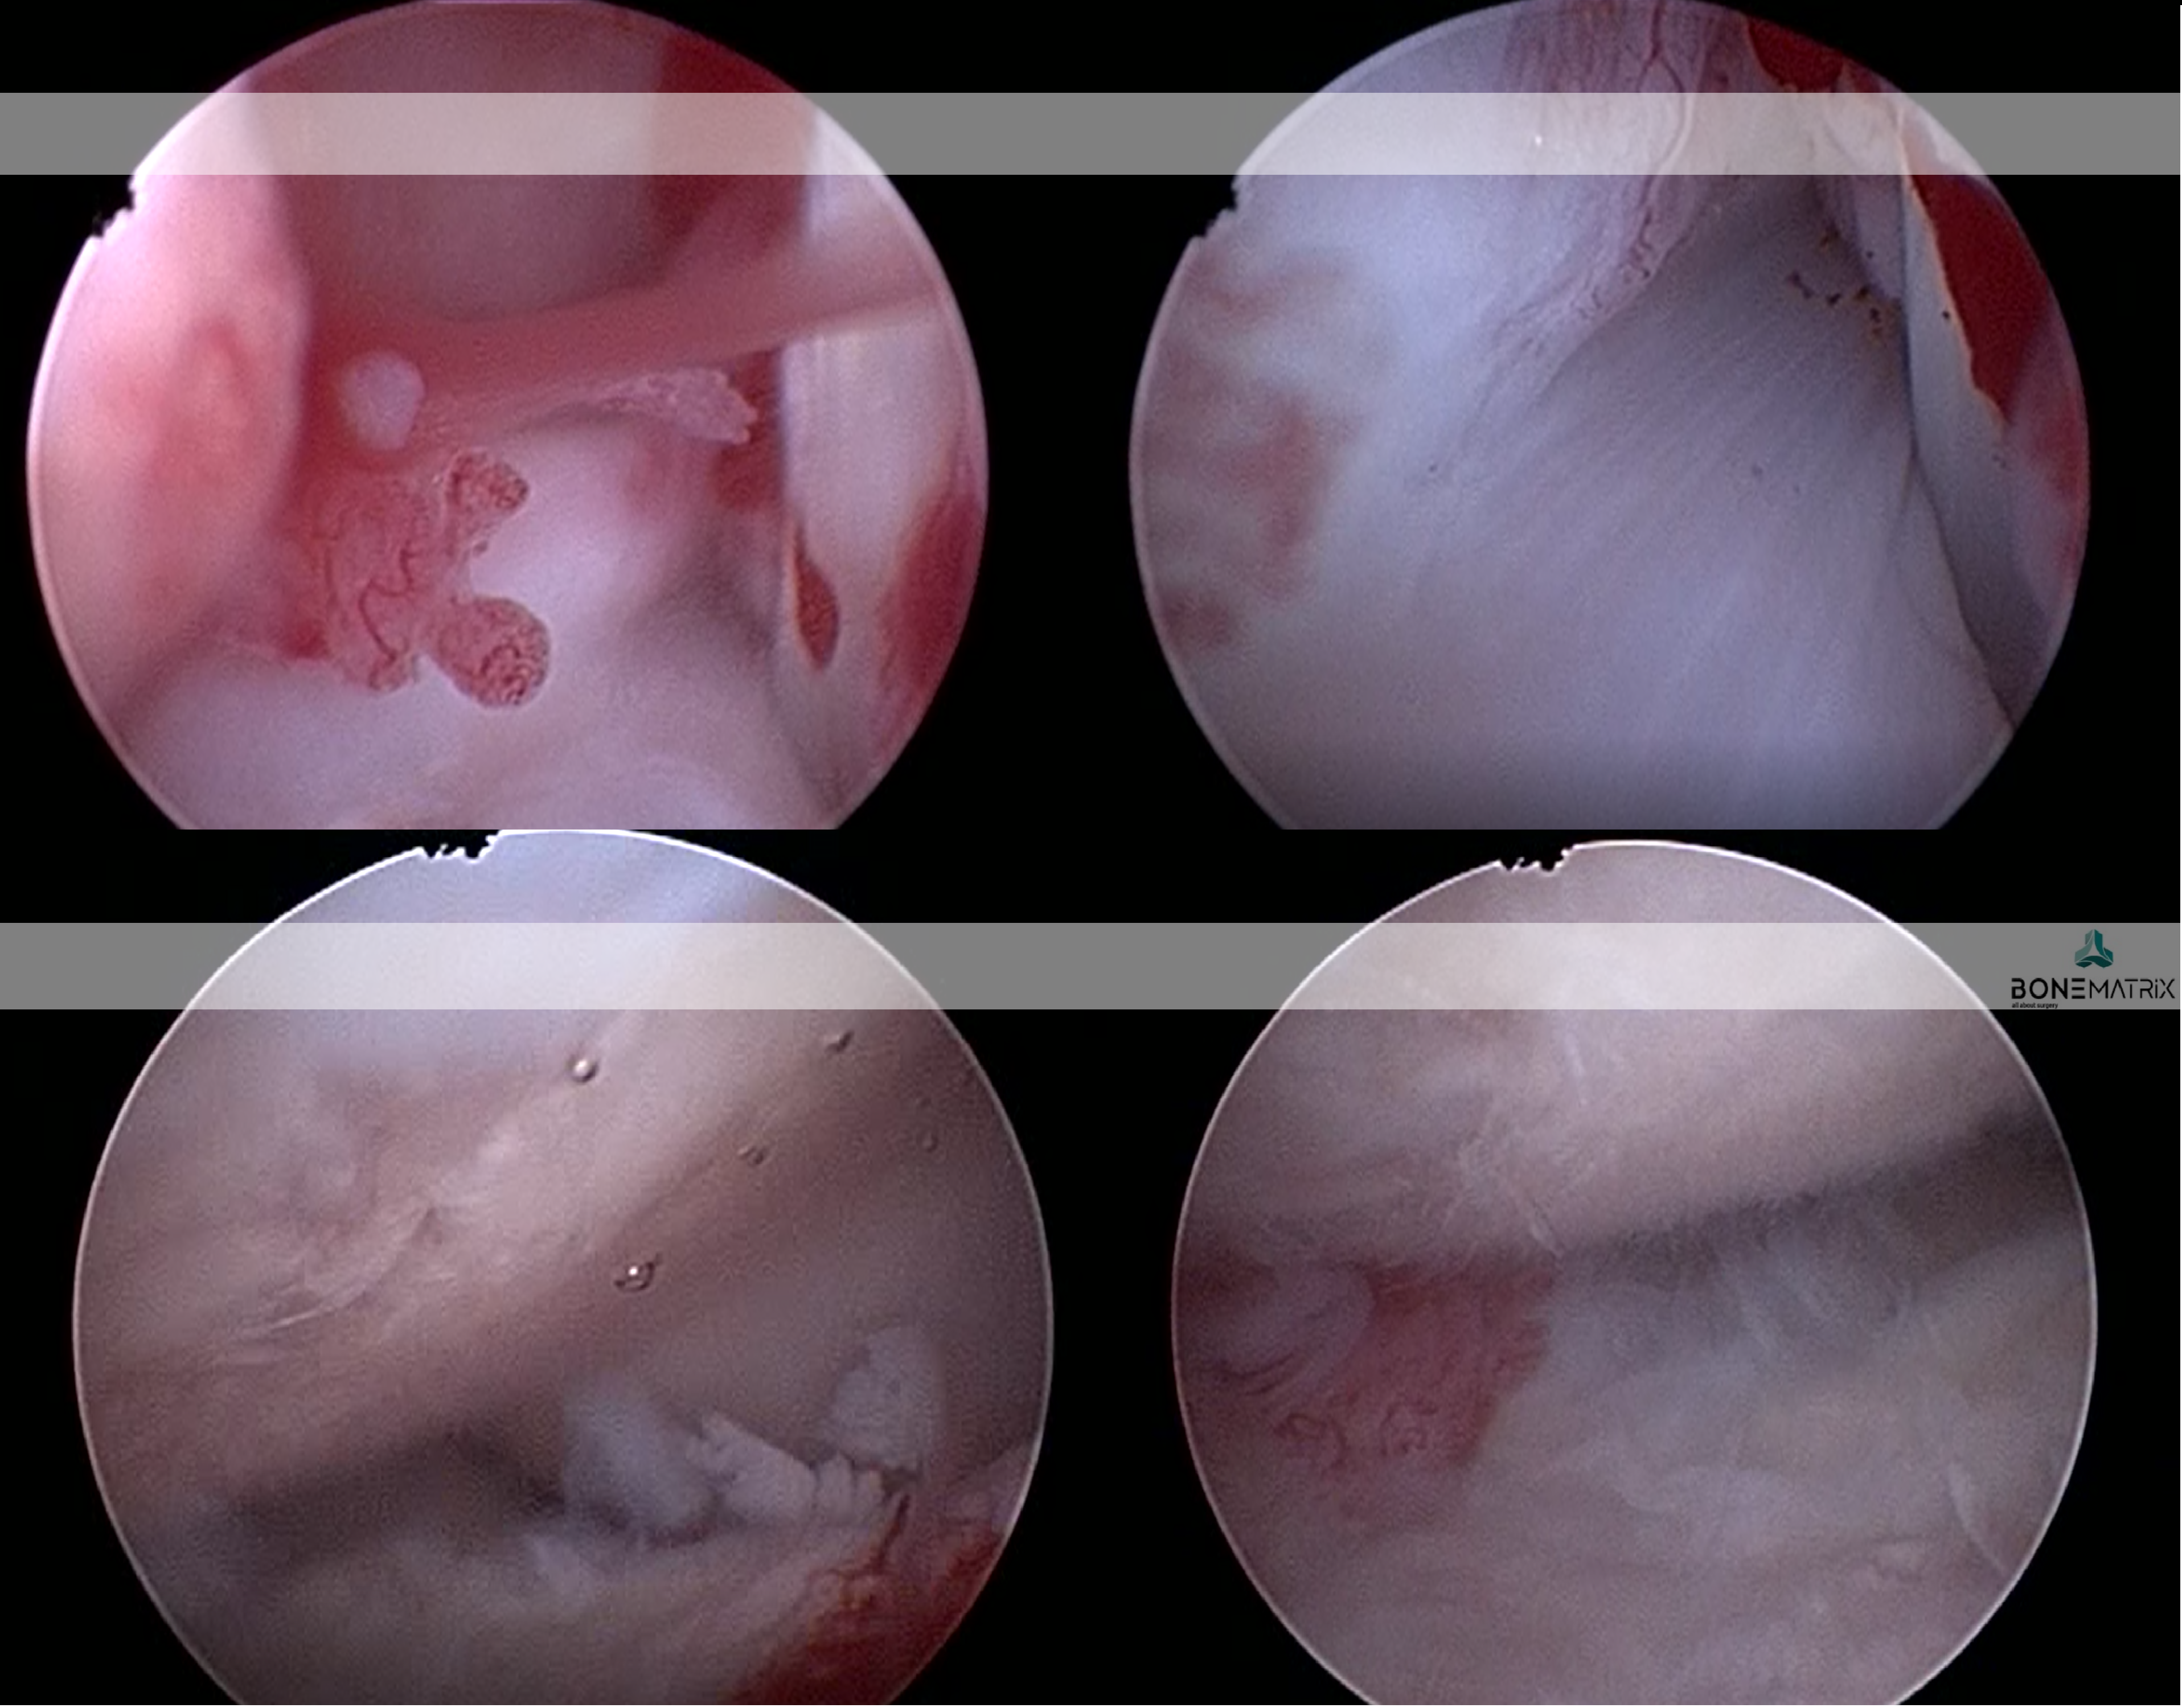

A artroscopia é um procedimento que pode ser utilizado como técnica diagnóstica e terapêutica.

A técnica consiste na abertura de dois a três pórticos de trabalho (orifícios de 1.9 a 2.4mm), através das quais são colocados:

- Uma câmara magnificadora que nos permite visualizar com elevado detalhe o aspeto do interior da articulação, nomeadamente a saúde da cartilagem, ligamentos e capsula articular;

- Instrumentos cirúrgicos necessários para a execução dos tratamentos das lesões identificadas.

Este procedimento é minimamente invasivo o que permite fazer intervenções cirúrgicas com uma morbilidade mínima. Por esta razão os pacientes apresentem menos dor no pós-operatório, maior amplitude de movimento e um retorno à função normal do membro que é quase imediata. Pelo facto de ser pouco invasiva, podemos com segurança operar mais que uma articulação no mesmo ato cirúrgico. Em alguns casos, a artroscopia está também associada a uma maior rapidez do procedimento, permitindo um menor tempo anestésico.

São várias as abordagens terapêuticas que podem ser feitas através deste procedimento. Entre estas estão, a remoção de “flaps” em lesões de OCD, remoções de partes danificadas de menisco, remoção de fragmentos de processo coronóide ou mesmo a remoção subtotal do processo coronóide (cotovelo).

Entre as abordagens diagnósticas podemos incluir procedimentos como deteção de rotura parcial de ligamento cruzado cranial (joelho), lesão do tendão bicipital (ombro), identificação de lesões de OCD e visualização de diferentes graus de degeneração articular.

Apenas serão visíveis 2 ou 3 pontos cutâneos na articulação, não sendo colocado qualquer penso ou tala. Uma vez que o procedimento é mesmo pouco invasivo, ainda que sejam operadas duas, ou mesmo três articulações no mesmo procedimento, o seu animal será capaz de usar os membros confortavelmente, caminhado sensivelmente da mesma forma que chegou até nós. Consoante o caso, as vantagens do procedimentos artroscópico podem ser apreciadas nos primeiros dias/semanas após a intervenção.